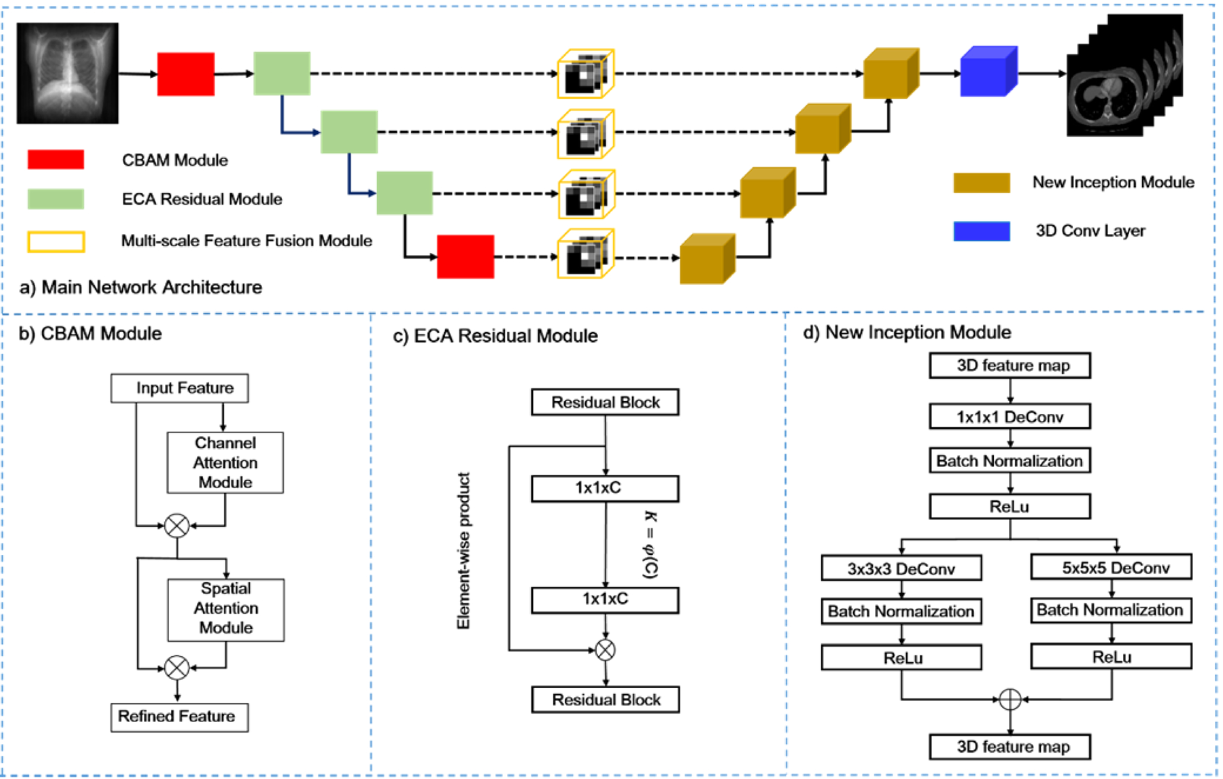

Computerized Medical Imaging and Graphics (CMIG), 2022.

Zhiqiang Tan, Jun Li, Huiren Tao, Shibo Li, Ying Hu.

[paper]

- This project focuses on exploring techniques for reconstructing 3D CT images from 2D X-rays.

- Project worked at Shenzhen Institutes of Advanced Technology, Chinese Academy of Sciences.